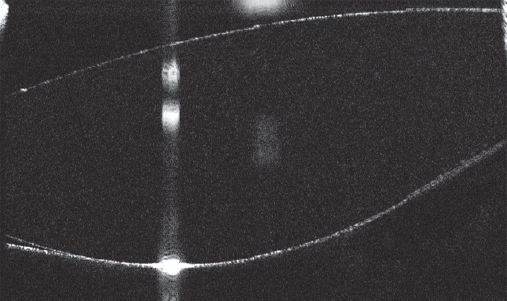

In all eyes, on day 1 and day 7 after PE, the IOL–PC interface was examined on the RS3000 Advance device (Nidek, Japan) to assess the IOL contact with the capsule (Figs. 1–3).

Fig. 1. Absence of contact between IOL and posterior lens capsule / Рис. 1. Отсутствие контакта интраокулярной линзы с задней капсулой хрусталика